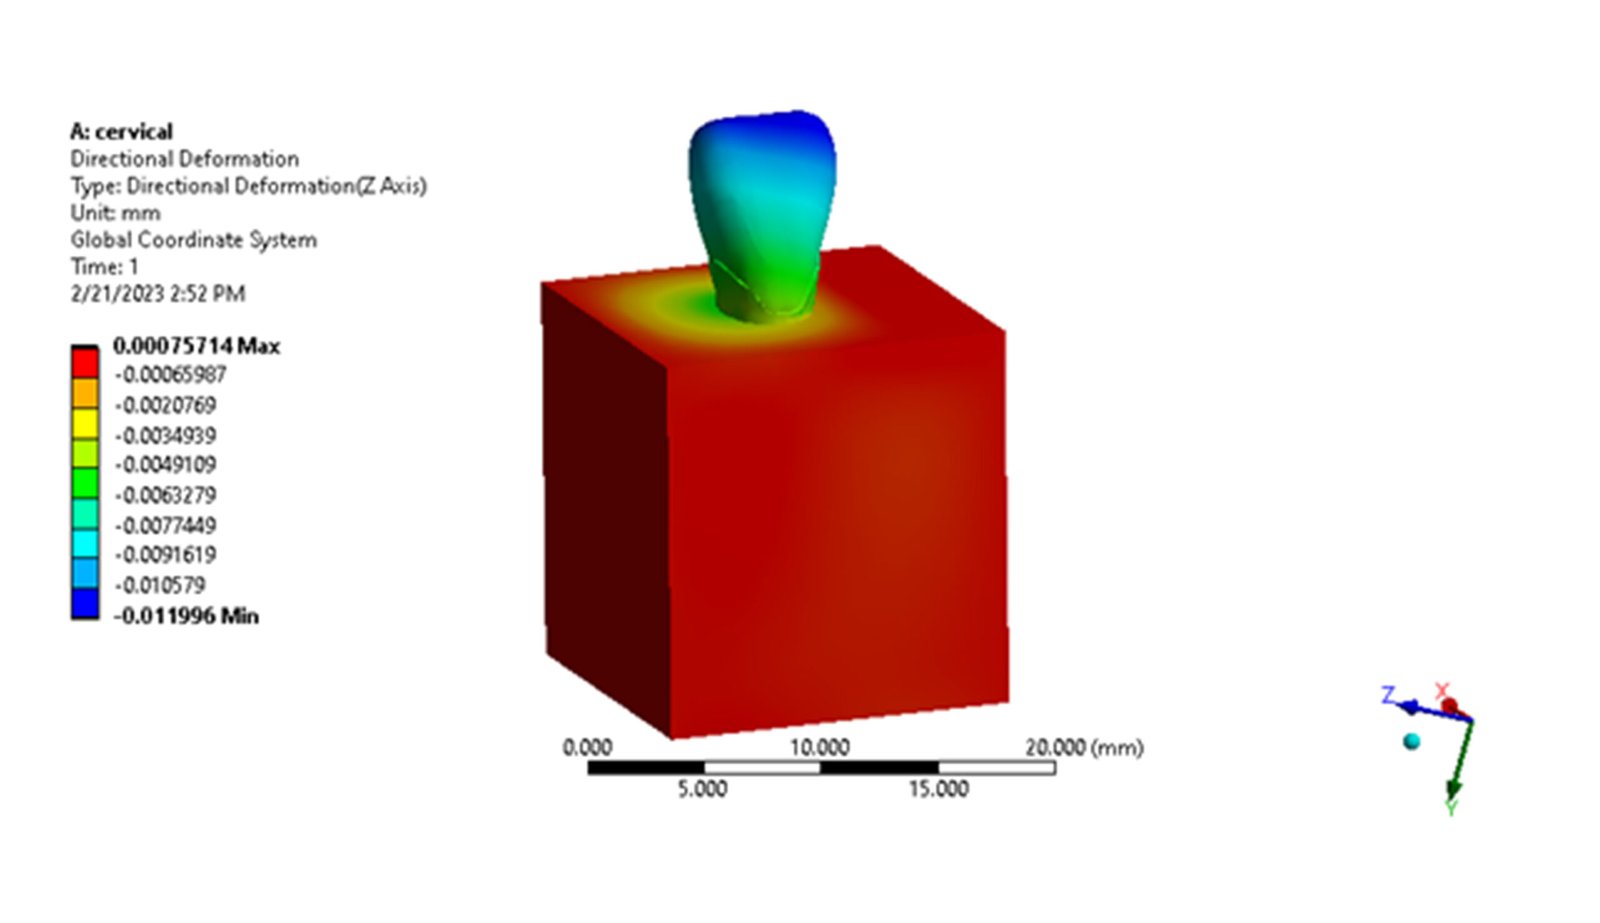

The Endodontic FEA section evaluates the biomechanical performance of root canal–treated teeth, endodontic tools, and reinforcement strategies. Through precise material characterization and micro-CT–based superimposition, we assess fracture risk, stress pathways, and instrument fatigue under various clinical scenarios. These simulations guide the selection of safer instrumentation techniques and restorative strategies. Our goal is to enhance predictability and reduce procedural complications.